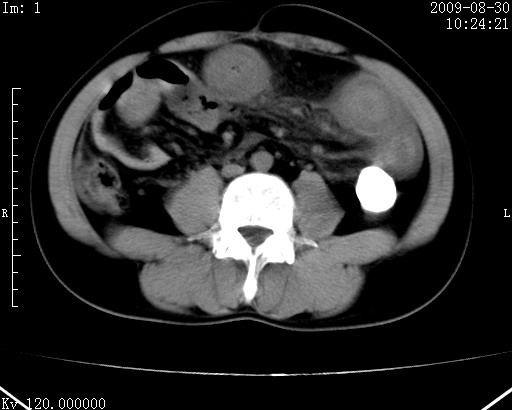

患者唐某,男31岁,已婚,本地务农。

自述入院前两天一次进食较多冷饮之后,出现阵发性上腹部疼痛,次日加剧伴恶心、呕吐,呕吐后症状稍减轻。食欲差。大便每天1-2次,量少,暗红色水样。小便赤。无畏寒、发热、咳嗽等呼吸道症状。无高血压及胃病史。

检查:体温、血压及脉搏正常.皮肤无黄染,浅表无淋巴结肿大。左腹肌紧张,左上腹有压痛,无反跳痛,可触及包块。

生化:钾、钠、氯、钙、ph正常,总胆红素和直接胆红素稍高,空腹血糖稍高。

尿淀粉酶:1256 u/l(正常60-401)。

血常规:wbc 22.4x109/l gr88% ly9.6%其余基本正常。

胃镜:急性胃炎。立位腹平片:未见异常。

下面是ct平扫,降结肠内是对比剂。

术前影像诊断:上段空肠急性缺血性坏死并腹水。建议手术治疗。

术中见上段空肠约70cm长范围坏死,从屈氏韧带远端约10cm处开始。坏死肠管肿胀变形变色,管壁明显环形增厚,部分聚成大肿块,无扭转和套叠。肠系膜上动脉分支内广泛泥沙状血栓。肠切除。

临床诊断:肠系膜上动脉梗塞并急性肠坏死。

开始时我们科也有人认为是套叠,最后统一意见,不考虑肠套。我们看到的“靶征”,“晕圈征”,“双圈征”实际上只是单根肠管的横断面。坏死肿胀后肠壁各层的密度不一样。

左侧腹小肠腔管壁明显增厚,部分内示靶征,走行异常,部分肠系膜绳样改变,肝包膜下及肠间较多液体密度,然梗阻近端肠腔积气不明显。

考虑;肠扭曲伴肠坏死。